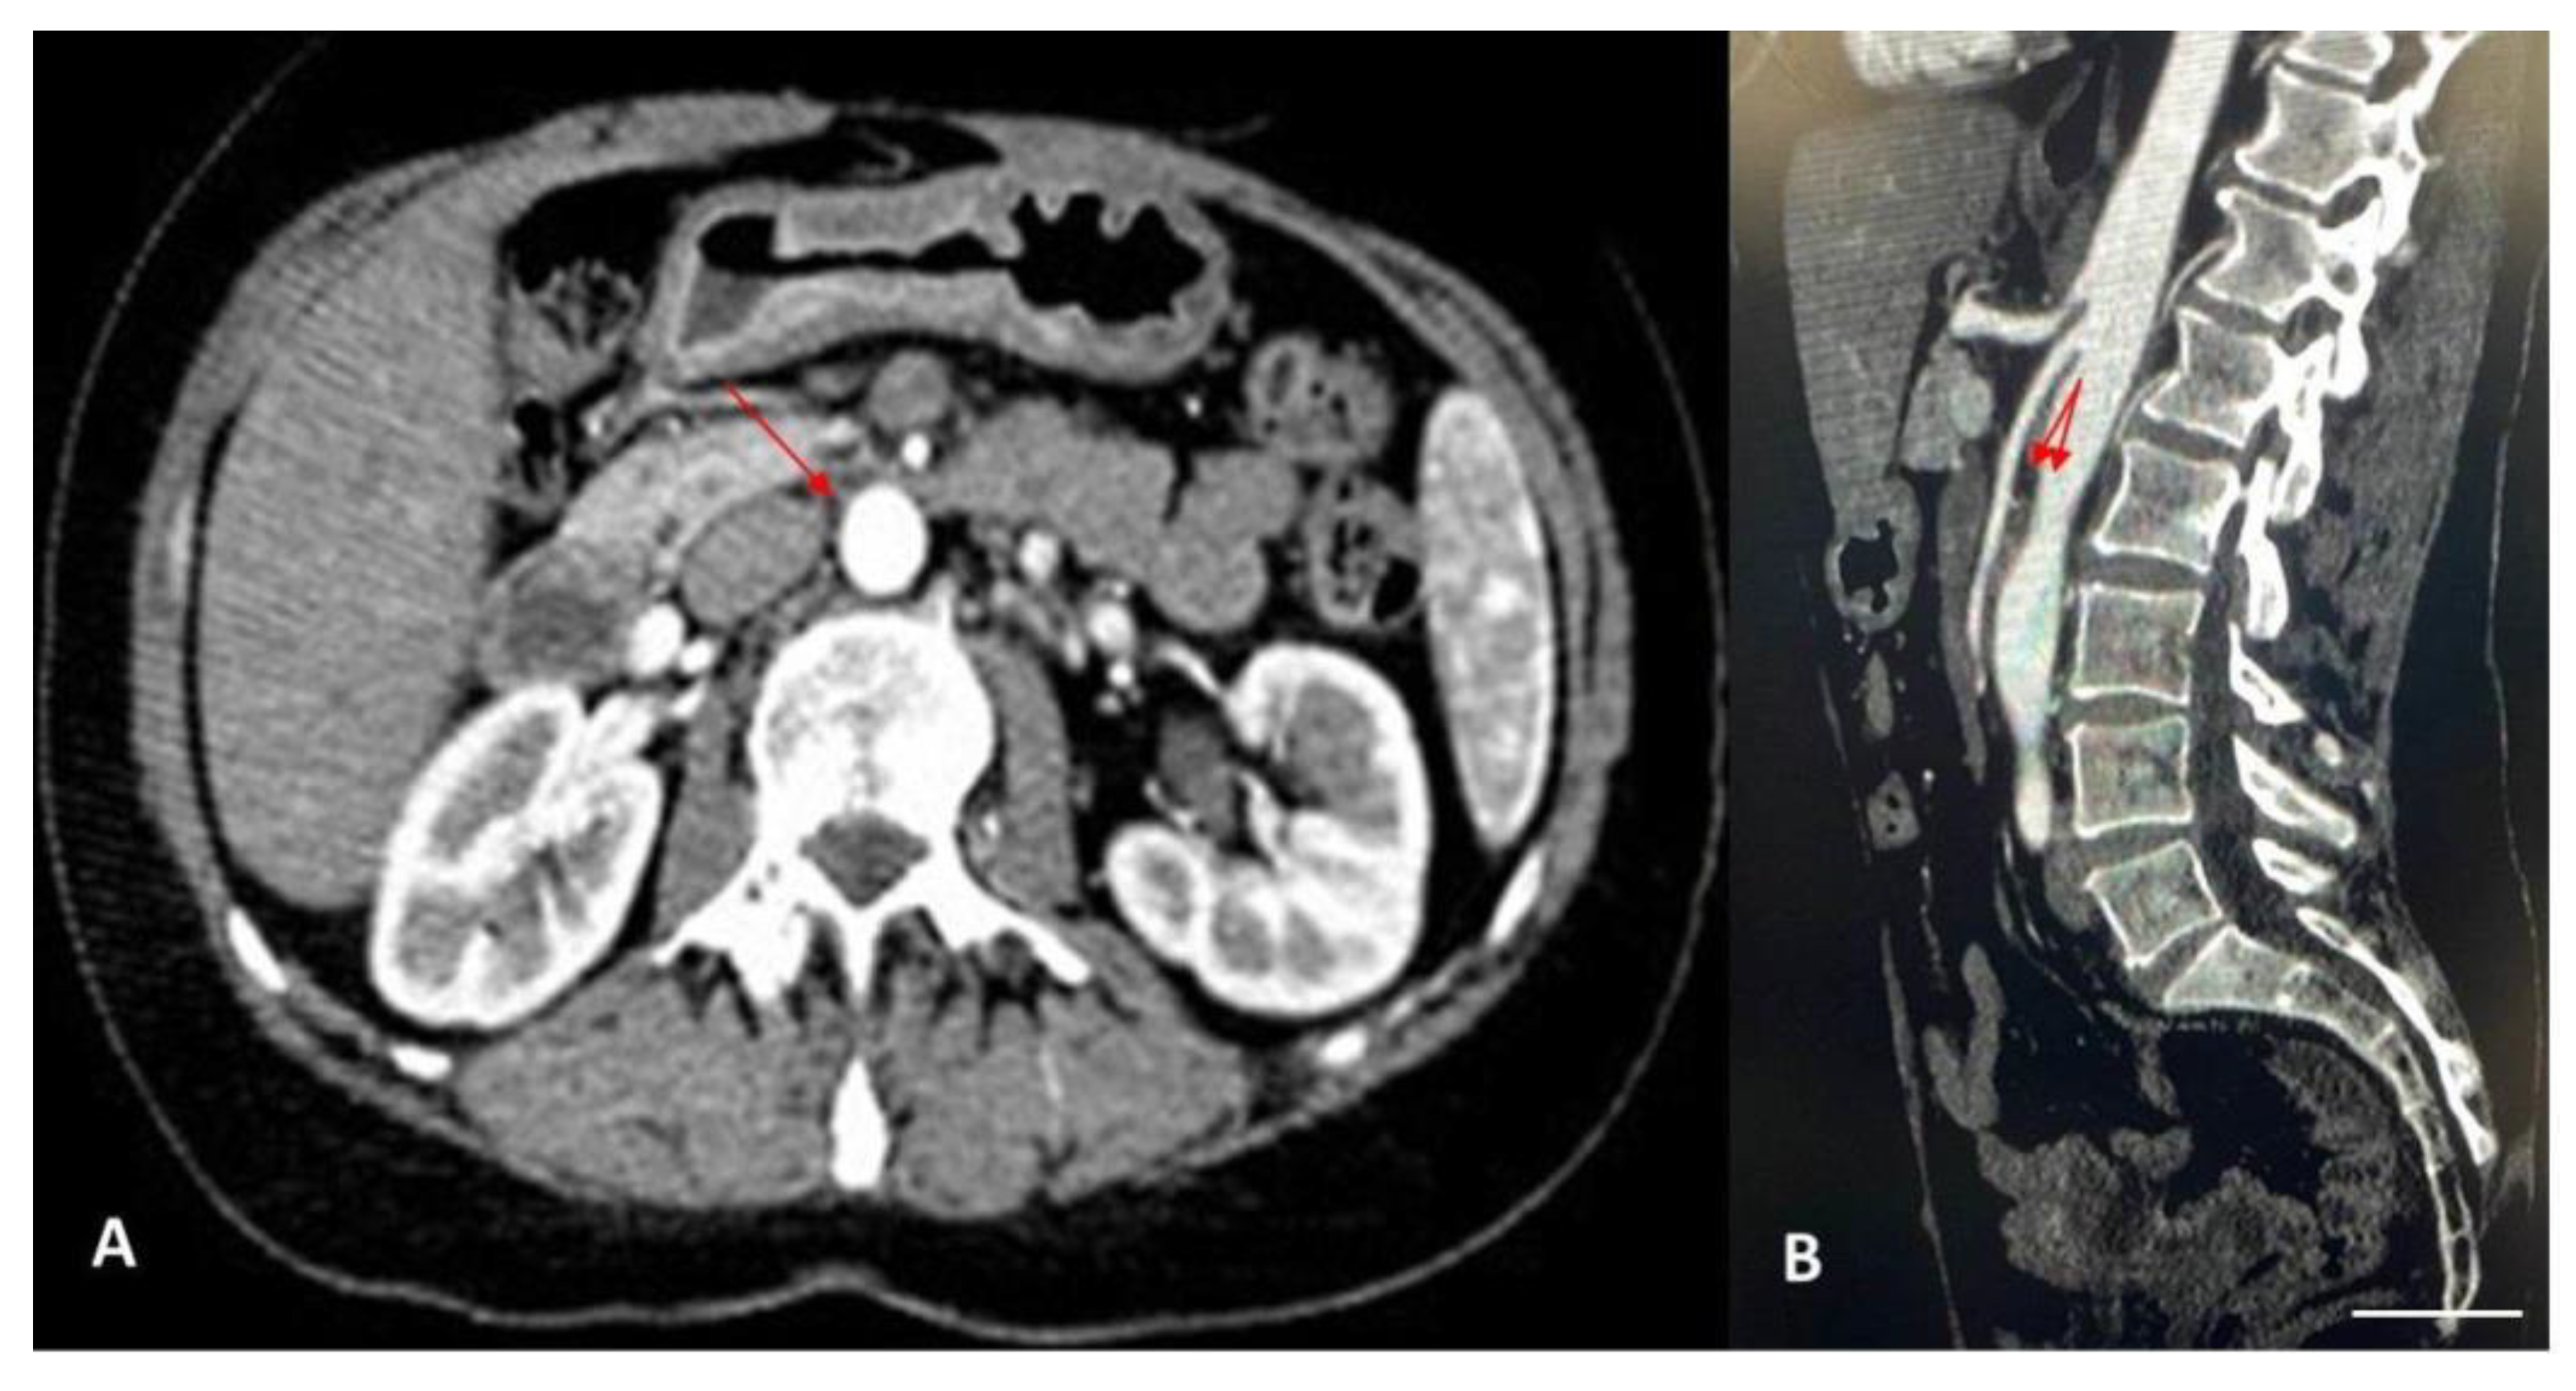

2. Case Report